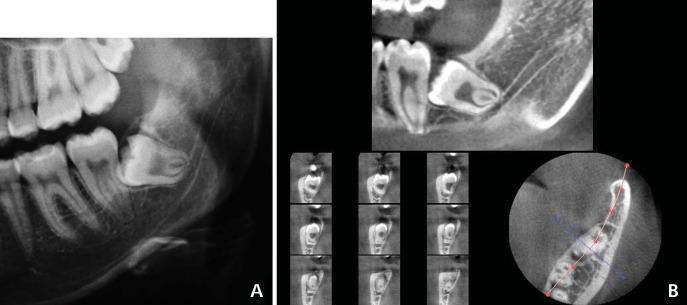

Preoperative radiographic assessment of the mandibular third molars is essential to prevent inferior alveolar nerve damage during extraction. The purpose of this study was to assess the reliability of panoramic signs of association between the roots of teeth and the canal, and to compare the panoramic signs with cone beam computed tomography (CBCT) findings.

CBCT images of 132 impacted mandibular third molars were evaluated to determine the association of the root to the canal. The CBCT findings were compared with the corresponding panoramic images. Logistic regression analysis was used to define the diagnostic criteria of the panoramic images.

AMONG THE PANORAMIC SIGNS, LOSS OF THE CORTICAL LINE WAS THE MOST FREQUENT RADIOGRAPHIC SIGN PREDICTING ASSOCIATION (SENSITIVITY: 79.31). Contact of the tooth with the canal was observed in all cases in which the loss of cortical line of the canal or darkening of the roots was found on the panoramic radiographs.

Darkening of the roots and loss of the cortical line on panoramic radiographs might be highly suggestive of the risk of nerve injury.

下颌第三磨牙术前的影像学评估对于防止拔牙过程中下牙槽神经损伤至关重要。本研究的目的是评估牙根与神经管之间关联的全景征象的可靠性,并将全景征象与锥形束计算机断层扫描(CBCT)结果进行比较。

对132颗下颌阻生第三磨牙的CBCT图像进行评估,以确定牙根与神经管的关联。将CBCT结果与相应的全景图像进行比较。采用逻辑回归分析来确定全景图像的诊断标准。

在全景征象中,皮质线消失是预测关联最常见的影像学征象(敏感性:79.31)。在全景片上发现神经管皮质线消失或牙根变黑的所有病例中,均观察到牙齿与神经管接触。

全景片上牙根变黑和皮质线消失可能高度提示神经损伤风险。